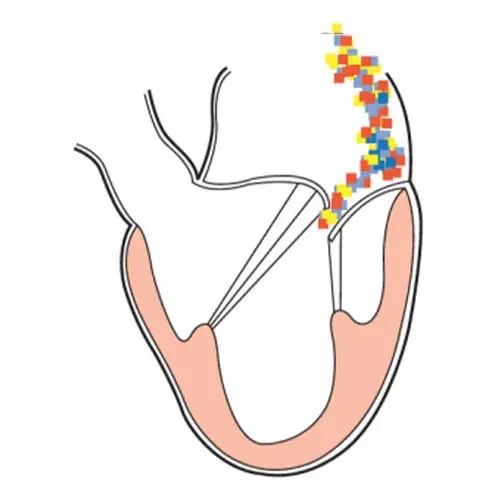

此培训为MAYO诊所推出的心内科fellow系列培训之一,主要目的是能够使大家学习到AMI以后心脏机械并发症的识别和诊断,还有ACS的非心脏的并发症的表现,以及临床中存在与ACS临床上有相似之处的非心脏疾病。 急性心肌梗死后出现的并发症,分为心脏性和非心脏性的,心脏并发症又包括心电学方面的并发症以及机械并发症,非心脏性并发症包括血栓栓塞和出血,还可能出现与心包相关的并发症。 心脏机械并发症包括就是破裂性和非破裂性的2类,破裂性并发症包括游离壁破裂、室间隔穿孔和乳头肌断裂,其中游离壁破裂既可能是直接的穿孔,也可以是亚急性破裂形成假性动脉瘤这样包容性的破裂。而非破裂性机械并发症包括严重的左室心力衰竭,右室梗塞,左室壁动脉瘤以及缺血性二尖瓣反流。 从根本上来说,这些严重并发症的发生都与心脏的泵功能衰竭有关,泵功能的衰竭造成了血流动力学不稳定以及基线的电不稳定性。 第一节:非破裂性机械并发症 非破裂性机械并发症,即严重的左室心力衰竭——心源性休克,右室梗塞,左室壁动脉瘤以及缺血性二尖瓣反流。 1、 心源性休克:在心梗发生时,发生心源性休克的主要原因就是大面积的心肌梗死,那么如果要导致心脏泵功能衰竭,左室心肌质量至少要损失40%以上。其他导致心源性休克的原因还有右室梗塞、心脏破裂以及快速和缓慢性心律失常。 2、 右室梗塞:也是导致心源性休克发生的重要原因。在下壁心梗的患者中,大概有33%的患者同时也发生右室梗死,这种情况多见于RCA近端闭塞,与高死亡风险相关。在所有下壁STEMI者中都要考虑是否同时存在RV梗塞,心电图V1和RV4导联ST段抬高超过1mm为其特异性心电图改变(图1)。 图1. 右室梗塞的心电图表现 3、 右室梗塞为什么会导致患者发生心源性休克呢?从病理生理上讲,右室急性缺血时会致其收缩不良,导致RV每搏输出量和峰压降低,继而是左室前负荷降低,心输出量降低;另一方面,急性缺血还同时使右室舒张功能受损,此时右心充盈压显著增加,并且由于右室急剧扩张,会在心包内占据很大体积,使得心包内压力显著增加,这些综合造成的结果使RV和LV的充盈减少。左心充盈压下降而右心压力不断升高,最终导致低血压、肺血流减少、颈静脉压升高,其临床结果可能类似于心包填塞以及缩窄性心包炎。 4、 左室壁动脉瘤(图2):首先提出一个问题供大家思考,以下有关左室壁动脉瘤的说法哪一个是正确的?1左室壁动脉瘤只局限于心内膜下;2有一个相对狭窄的颈部;3是否都与前壁心梗有关;以及4容易有血栓的附着,并且心包是组成瘤壁的一部分。实际上,左室壁动脉瘤在STEMI后的发生率<5%,前壁梗死的患者更易发生,及时进行再灌注治疗可以降低其发生率。它突出于心腔外侧,瘤壁就是左室壁,颈部和底部的比例大约是1:1,可以出现附壁血栓。所以上述说法中只有3是正确的。 图2. 左室壁动脉瘤示意图,O;颈部,D:底部,LA:左心房,LV:左心室,AO:主动脉 5、 缺血性二尖瓣反流:为心梗后左室重构所致,表现为乳头肌移位、乳头肌功能不良使瓣叶活动受限以及瓣环扩张(图3)。治疗的焦点集中于及时的再灌注治疗、利尿剂的应用和后负荷的降低,如果遗留严重的二尖瓣反流,则会导致心梗后的远期生存率下降。 图3. 瓣环扩张(A)、乳头肌功能不良致瓣叶活动受限(B)导致大量MR 第二节:破裂性机械并发症 破裂性并发症包括游离壁破裂、室间隔穿孔和乳头肌断裂,其中游离壁破裂既可能是直接的穿孔,也可以是亚急性破裂形成假性动脉瘤这样的包容性破裂。大多数破裂性并发症都发生在AMI的第一个24小时之内,剩余的则发生在1周之内。通过超声心动图可以发现MI的机械并发症,包括急性乳头肌断裂、下段室间隔断裂、上段室间隔断裂以及二尖瓣脱垂。 1、 乳头肌断裂所致二尖瓣反流(图4):乳头肌断裂常发生在MI后的2~7天,急性缺血事件发生时,从心外到心内的压力梯度增加,心内灌注降低,乳头肌属于心内结构,缺血的敏感性增加。一旦出现需要外科手术治疗。 图4. 乳头肌断裂(箭头所示) 2、 室间隔缺损(图5):属于MI后的罕见并发症,多于梗死后3~5天发生,在梗死后即刻或者第一个24小时内就可以发生,部分与患者进行的纤溶治疗有关。由于再灌注治疗的开展,目前发生率已经由2%降至0.2%。破裂发生在健康心肌和坏死心肌的交界处,在前壁心梗时,缺损位于室间隔心尖部,下壁心梗时缺损则位于下-后间隔基底段,RV梗死及功能失常者预后不良。 图5. 前壁心梗(A)、下壁心梗(B)所致不同部位室间隔穿孔 3、 游离壁破裂:急剧的、常为致死性机械并发症;发生率<1%;MI后死亡约8~24%是由此而造成;通常在梗死后的5天内发生。好发因素包括1首次心梗,2前壁心梗,3老年患者以及4女性。 4、 亚急性破裂:是一种特殊类型的游离壁破裂,占所有游离壁破裂患者的约1/3,是因为附壁血栓和心包覆盖了穿孔部位所致,局部表现为假性动脉瘤(图6),临床上常比较隐匿,并且可能仅通过UCG发现,因此任何超声发现的心脏周围局部积液都需要引起怀疑并详细扫查。与真性动脉瘤(即左室壁动脉瘤)不同,假性动脉瘤的颈部狭窄,颈部与底部的比值<0.5,心包是瘤壁的组成部分。亚急性破裂的进展常是难以预测,可以进展至完全破裂乃至心包填塞,因此需要外科治疗。 图6. 左室假性动脉瘤示意图,O;颈部,D:底部,LA:左心房,LV:左心室,AO:主动脉 第三节:AMI的非心脏并发症 AMI的非心脏并发症主要包括血栓栓塞和出血,以及心包并发症。那么下面关于左室血栓的说法哪个是正确的呢?1下壁心梗更为常见,2如果不予治疗栓塞风险可达50%,3栓塞的风险取决于血栓的移动性和是否凸出于腔内。左室血栓常(图7)见于大面积前壁心梗,在再灌注前时代其发生率可高达40%,有再灌注治疗后这一几率已降至4~15%;经胸超声心动图是发现LV血栓的第一选择;心脏MRI的敏感性更高,但与超声心动图的特异性相似。由于心梗后不运动和运动障碍的室壁区域存在静止血流,因此如容易在局部形成附壁血栓。如果梗死部位为心尖部,且左室EF值减低达<30%,则存在血栓栓塞的高风险。如果未治疗,左室血栓发生栓塞的风险为10~15%,这一风险的高低还取决于栓子的移动性和是否突出于心腔内,早期且持续的抗凝治疗(3~4个月)可以降低栓塞风险。 图7. 左室心尖部附壁血栓 一图总结心脏机械并发症 第四节:类似ACS的非心脏疾病 通过一个有趣的病例,我们来学习一下在临床中可能存在类似于ACS表现的非心脏疾病。这是一个77岁老年女性,症状为头晕、恶心、呕吐,急诊CT除外了急性卒中,但心肌坏死标记物升高,心电图提示为Af、并且下壁前壁导联T波倒置,但超声心动图上仅表现为室间隔中下段至左室心尖部运动减低,没有看到下壁及前壁的运动异常。随后患者出现严重的高血压和心动过缓,并存在定向力、消化不良和眼球震颤,继续监测头CT及MRI,结果发现枕叶大面积脑梗。实际上,早在1947年,急性卒中所引起的ECG变化就已经被报道,病程中出现深大的倒置T波则被称为神经源性T波。在急性颅内事件发生时可以存在肌钙蛋白的升高以及心电图出现ST-T改变,在卒中的急性期,ECG诊断急性心梗的特异性会降低。 除急性脑血管病以外,以下疾病也会出现类似于ACS的临床发现,包括心电图异常和心肌坏死标记物升高,如特发性应激性心肌病,主动脉夹层,肺栓塞等等,需要及时进行诊断及鉴别诊断。 最后需要强调的是,超声心动图是发现AMI后心脏机械并发症的最重要检查,AMI发生后一周内必须行UCG检查以发现隐匿的高危并发症。